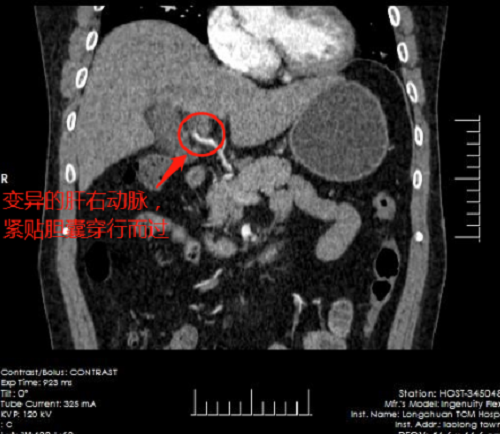

深圳市中医院派驻龙川县中医院的外科骨干李嘉硕士,检查后认为患者进行胆囊切除势在必行,但完善相关检查,发现患者存在三大手术难点:其一,患者过度肥胖,器官组织脂肪沉积,术中显露存在一定困难;其二,因多次腹痛频繁发作,胆囊充血水肿炎症偏重,渗出较多,解剖关系不清晰;其三最为重要,患者肝动脉变异,肝右动脉为右侧肝脏的主要供血动脉,多数均在肝门处稍低位进入肝脏,但患者肝右动脉显著降低至距离切除胆囊壁不足2毫米处汇入右侧肝脏,手术中一旦损伤此动脉,鲜血将喷射而出,后果不堪设想。根据综合评判,患者胆囊归类为四级胆囊,手术难度在胆囊切除术中属于最高级别,需要技术成熟的手术团队方可顺利切除。

与术前预想一致,患者因频发腹痛导致胆囊充血水肿僵硬,显露分离困难,且肝右动脉紧贴胆囊穿行汇入肝脏,外一科手术团队仔细辨认组织关系后分离胆囊,巧妙地避开了粗大搏动的肝右动脉,成功切除病变胆囊,术中出血不到20ml,手术顺利完成。